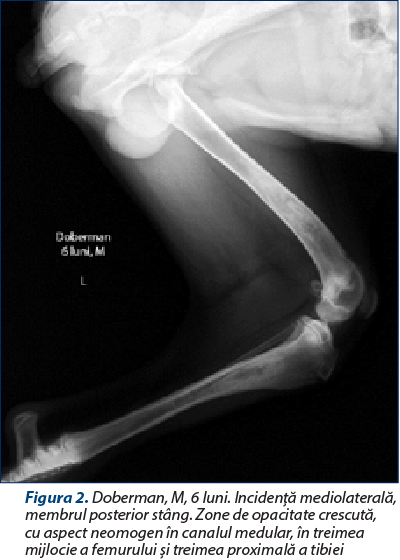

Modificările radiografice se prezintă într-o gamă variată de semne, în funcţie de momentul evolutiv al bolii. Boala prezintă trei faze (una precoce, una mijlocie şi una tardivă), din care prima fază este greu de surprins radiografic (Pollard şi Phillips, 2018; Kieves, 2021). Deşi poate afecta orice parte a diafizei unui os lung, de cele mai multe ori procesul debutează în apropierea orificiului arterei nutritive diafizare. Semnul iniţial este reprezentat de o scădere a opacităţii canalului medular în jurul orificiului arterei nutritive a osului (faza 1). Apoi, se produce o creştere focală a opacităţii endostului, rezultând zone bine delimitate în canalul medular, cu opacitate similară corticalei diafizare. Pe măsură ce boala evoluează, leziunile osoase progresează, focarele cu opacitate crescută fuzionează, transformându-se în focare cu aspect neuniform, difuz, cu tendinţă de extindere pe o zonă cât mai mare din canalul medular diafizar (faza a doua) (figurile 1 şi 2). Periostul din apropierea zonelor afectate poate deveni evident, constatându-se o reacţie periostală omogenă, fenomen observat la 15-50% din cazuri (Trostel şi col., 2003; Kieves, 2021). Ulterior, se constată că zonele din canalul medular îşi diminuează opacitatea şi dispar, astfel că, din punct de vedere radiografic, osul îşi recapătă aspectul iniţial (faza a treia) (Tudor şi Vlăgioiu, 2015). Examenul radiografic este necesar atât pentru confirmarea diagnosticului, cât şi pentru excluderea altor afecţiuni osteoarticulare. Diagnosticul diferenţial se face cu alte osteopatii ale tineretului, caracterizate prin şchiopătură şi sensibilitate osoasă, cum ar fi osteodistrofia hipertrofică, hiperparatiroidismul secundar nutriţional, rahitismul, osteomielita etc.

Figura 2. Doberman, M, 6 luni. Incidenţă mediolaterală, membrul posterior stâng. Zone de opacitate crescută, cu aspect neomogen în canalul medular, în treimea mijlocie a femurului şi treimea proximală a tibiei